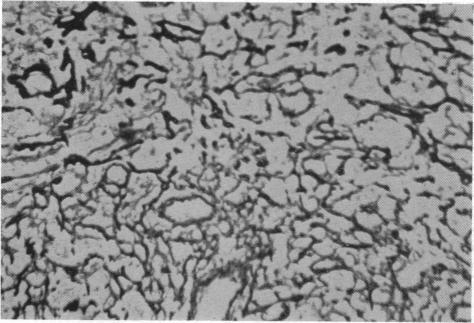

Case of Mesenteric Reticulosarcoma Associated with Gluten-sensitive Steatorrhoea.

Br Med J. 1961 Aug 19;2(5250):496-480.2. doi: 10.1136/bmj.2.5250.496.